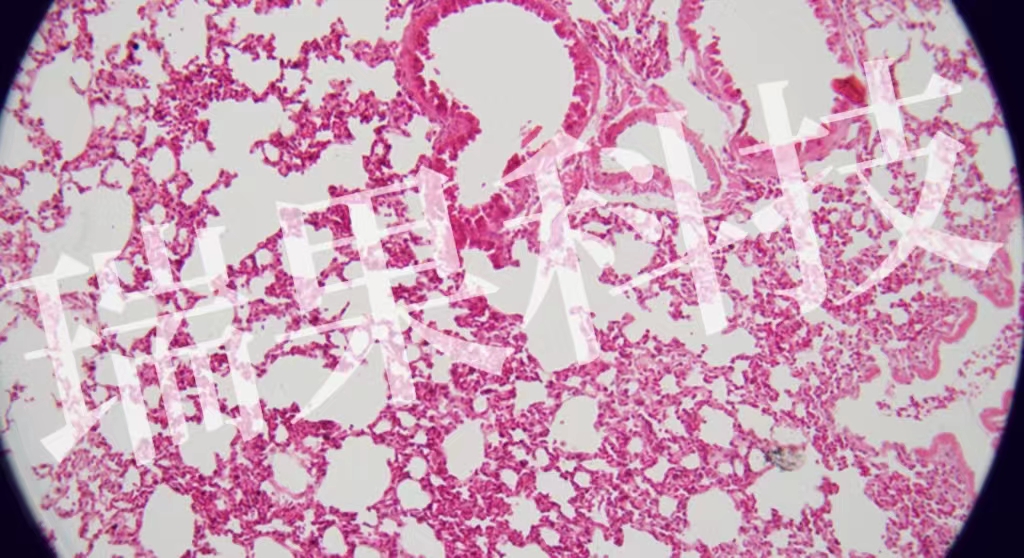

HE染色:蘇木精 - 伊紅染色法 ( hematoxylin-eosin staining ) ,簡(jiǎn)稱HE染色法 ,石蠟切片技術(shù)里常用的染色法之一 。蘇木精染液為堿性 ,主要使細(xì)胞核內(nèi)的染色質(zhì)與胞質(zhì)內(nèi)的核酸著紫藍(lán)色 ;伊紅為酸性染料 ,主要使細(xì)

HE染色:蘇木精 - 伊紅染色法 ( hematoxylin-eosin staining ) ,簡(jiǎn)稱HE染色法 ,石蠟切片技術(shù)里常用的染色法之一 。蘇木精染液為堿性 ,主要使細(xì)胞核內(nèi)的染色質(zhì)與胞質(zhì)內(nèi)的核酸著紫藍(lán)色 ;伊紅為酸性染料 ,主要使細(xì)胞質(zhì)和細(xì)胞外基質(zhì)中的成分著紅色 。HE染色法是組織學(xué)、胚胎學(xué)、病理學(xué)教學(xué)與科研中最基本、使用最廣泛的技術(shù)方法。

肺2-1-20x